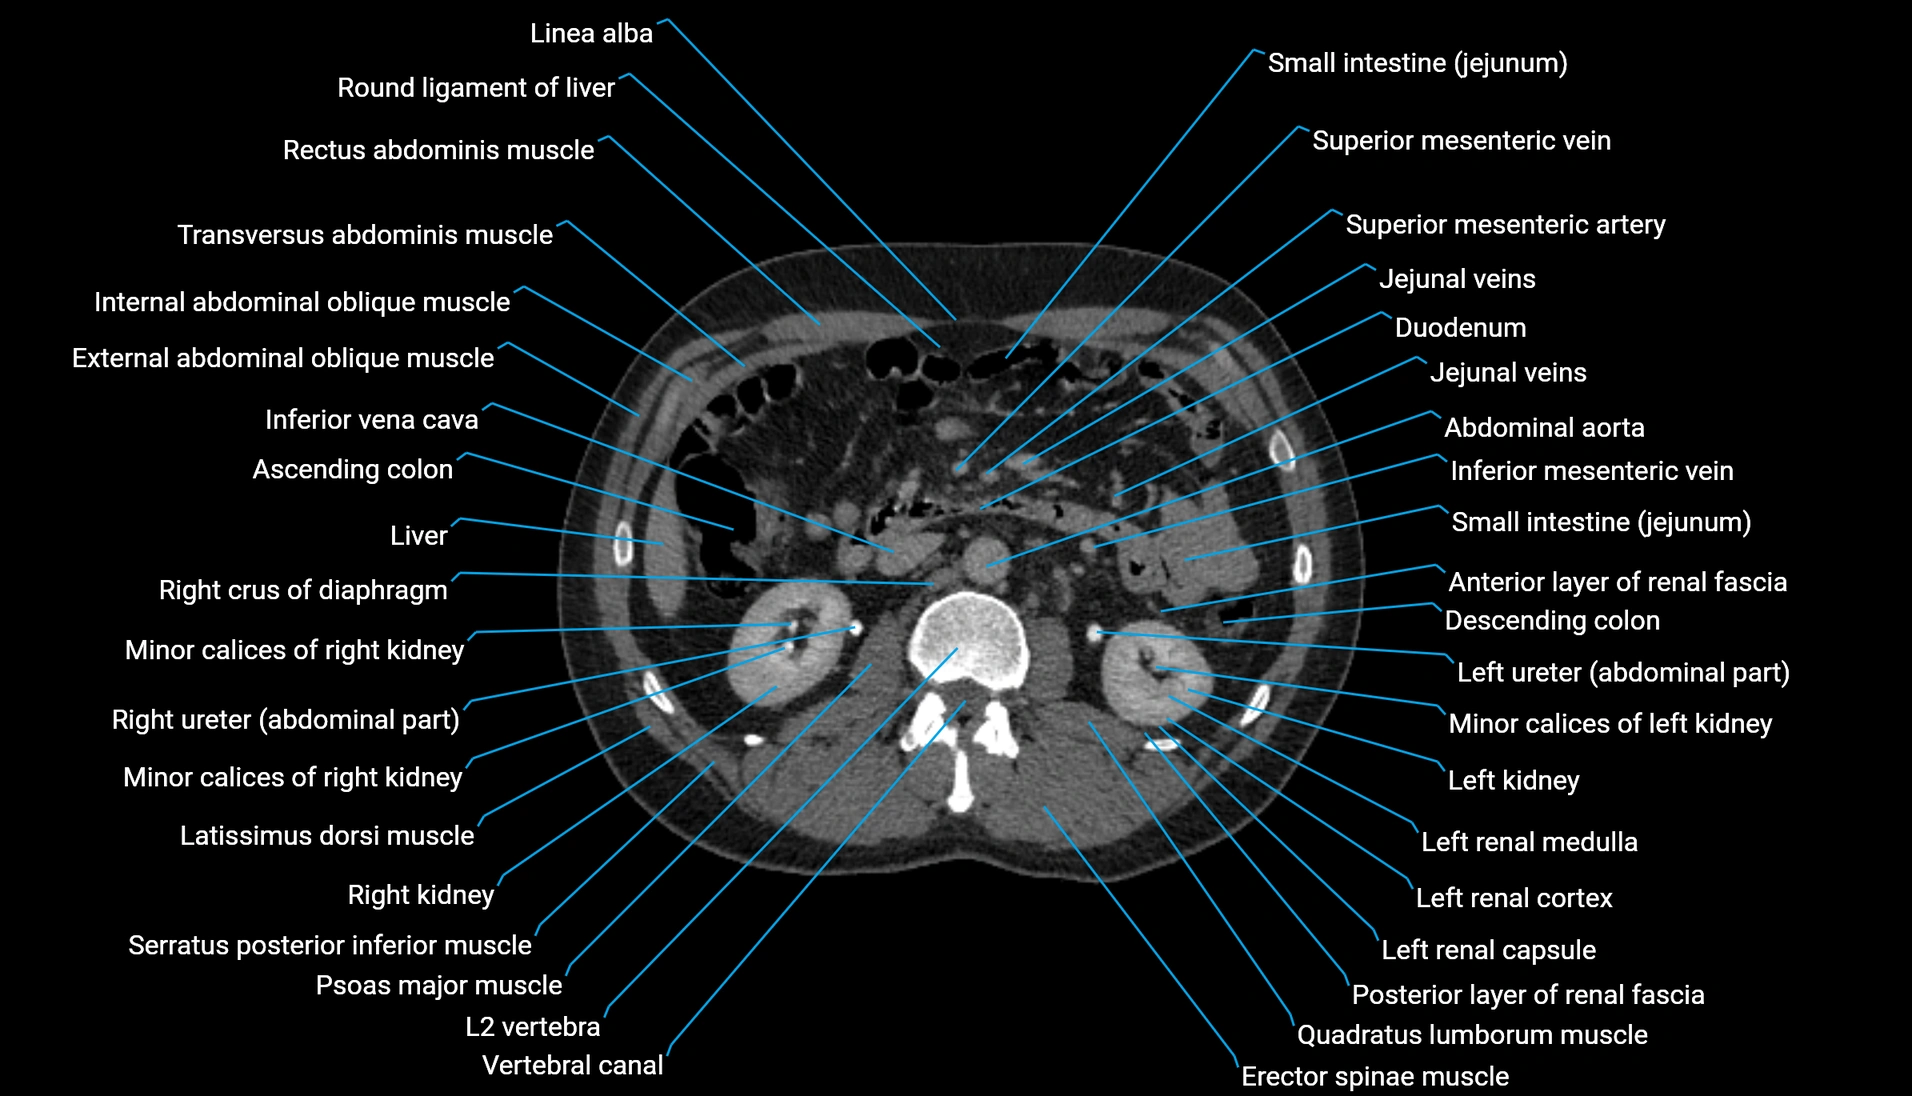

CT Appearance

Non-contrast CT:

-

Demonstrates cortical bone of acetabular rim in excellent detail

Detects fractures, dysplasia, retroversion, or bony overcoverage (pincer impingement)

3D reconstructions used in preoperative hip surgery planning

CT VRT 3D image

CT image